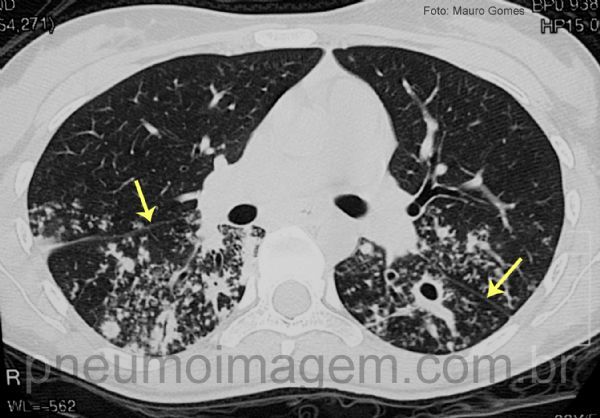

As lesões estendem-se pelos lobos superiores e inferiores, separados pela cissura (setas amarelas).

Cavidade no lobo inferior esquerdo. Numerosos nódulos centrolobulares bilaterais, indicando impactação de muco em vias aéreas terminais (bronquíolos) e provável disseminação broncogênica da tuberculose.

The lesions extend through the upper and lower lobes, separated by the cissura (yellow arrows). Cavity in the lower left lobe. Numerous bilateral centrilobular nodules, indicating impaction of mucus in the terminal airways (bronchioles) and probable bronchogenic dissemination of tuberculosis.